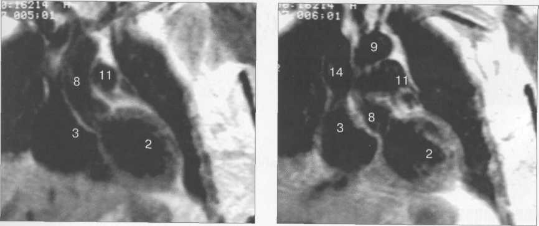

Рис. 9.48. MPT сердца. Сагиттальная плоскость.

Рис. 9.49. МРТ сердца. Двухкамерные сечения.

Рис. 9.50. МРТ сердца. Фронтальные сечения.

Рис. 9.51. МРТ сердца. Сечения по короткой оси левого желудочка.

Рис. 9.52. МРТ сердца. Четырехкамерные сечения.

На рис. 9.47—9.52 представлены Т1-ВИ наиболее часто используемых МР-сечений сердца.

Здесь и на рис. 9.48—9.52:

I — правый желудочек, 2 — левый желудочек, 3 — правое предсердие, 4 — левое предсердие, 5 — межжелудочковая перегородка, 6 — межпредсердная перегородка, 7 — задняя стенка левого желудочка, 8 — восходящая часть аорты, 9 — дуга аорты, 10 — нисходящая часть аорты, 11 — легочный ствол, 12 — правая легочная артерия. 13 — левая легочная артерия, 14 — верхняя полая вена, 15 — нижняя полая вена, 16 — трахея.